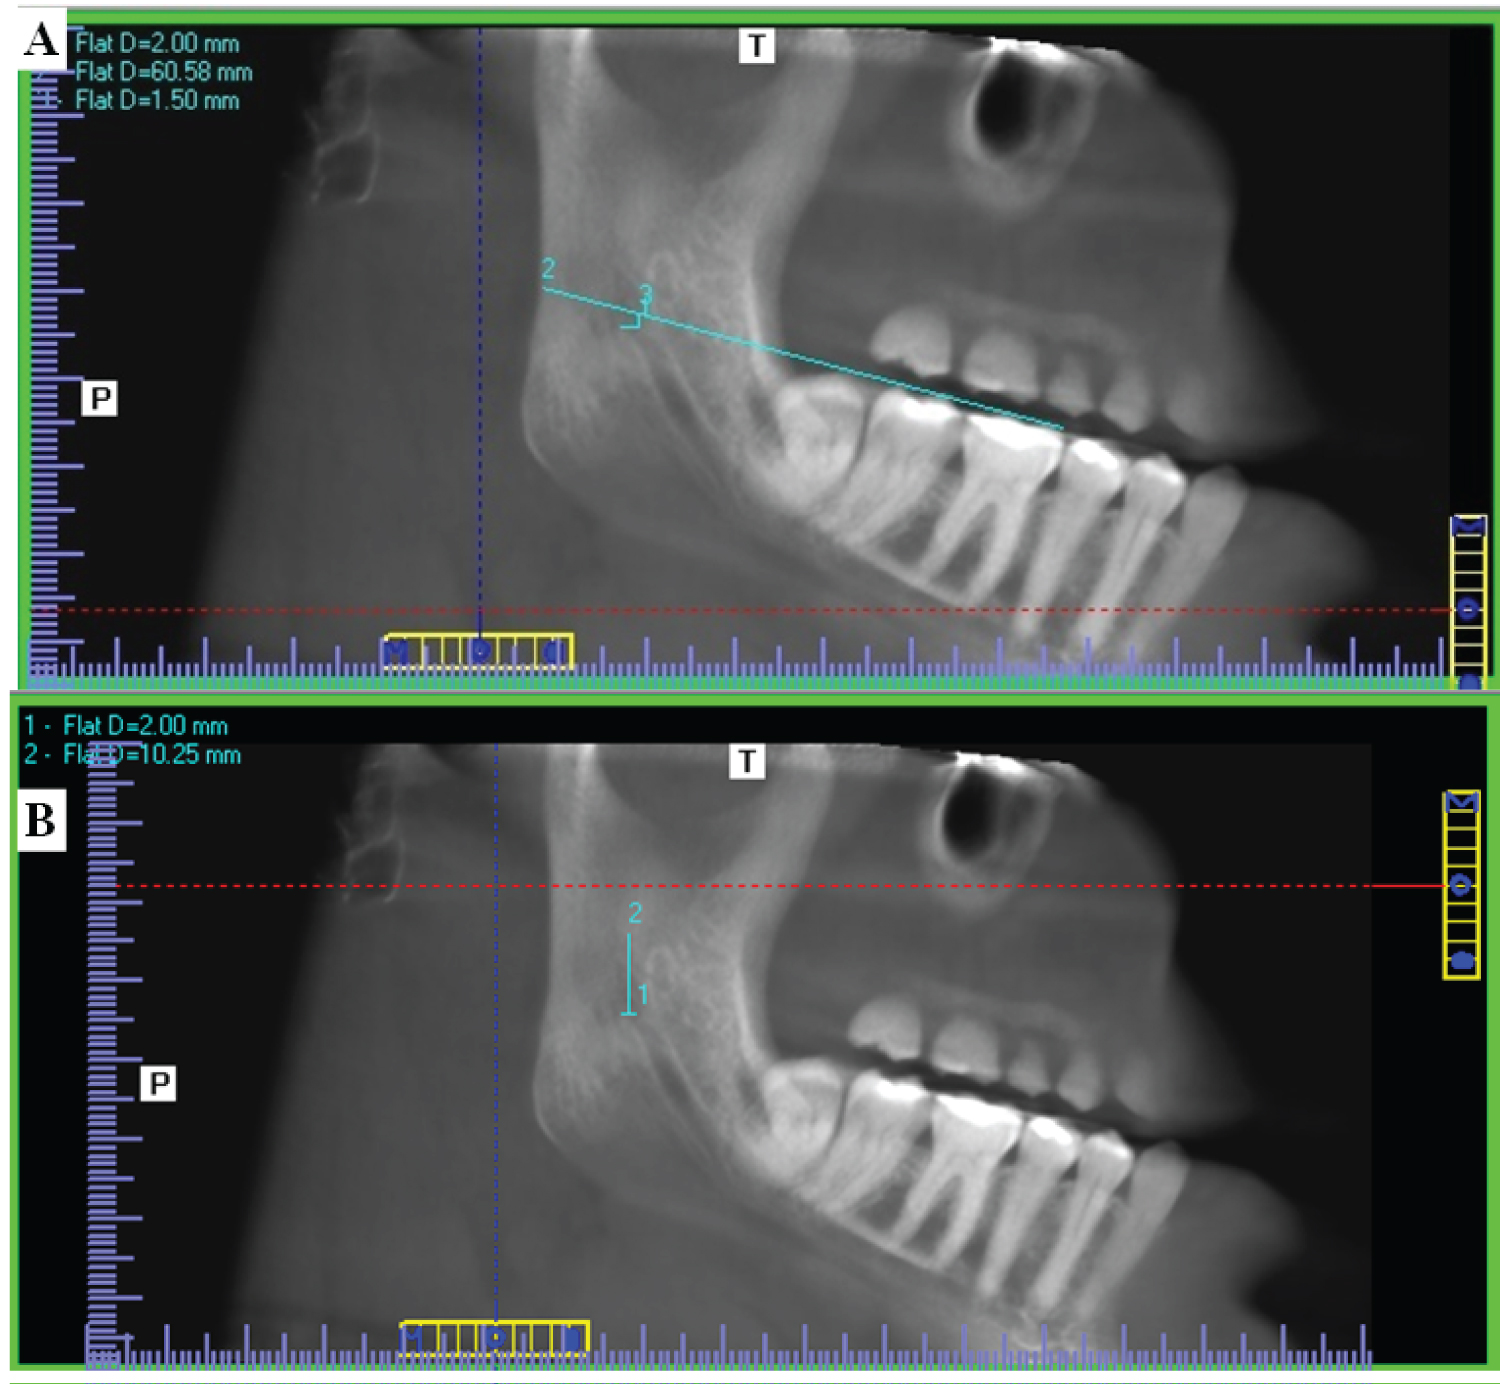

To measure distances MF-OP and MF-ARMT, In the coronal view, the axial plane was scrolled up to the slice that shows the widest pulp chamber of the mandibular first molar. In the axial view, the view rotated till the buccal wall of mandibular six parallel to sagittal plane, then the sagittal plane was moved to pass through the lingual wall of the mandibular first molar and also bisect the mandibular ramus as illustrated in (Figure 4A). In the axial view, the coronal plane was scrolled up to the first slice that shows the mandibular foramen completely surrounded by cortical bone. In the coronal view, the view was rotated till MF lingual wall parallel sagittal plane, then the sagittal plane was moved to pass through the lingual wall of the mandibular foramen as well as the mandibular condyle as illustrated in (Figure 4B). (Figure 5A and Figure 5B) show measurement of MF-OP and MF-ARTM from the standardized sagittal view.

Figure 4: A) Standardization of the axial view on I-CAT Vision software to measure MF-OP and MF-ARMT. The axial view that showed the widest pulp chamber of the mandibular first molar was rotated till the buccal aspect of mandibular first molar became parallel to the sagittal plane. The sagittal plane was then moved to pass through the buccal wall of the mandibular first molar and also bisect the mandibular ramus; B) Standardization of the coronal view that showed the mandibular foramen completely surrounded by cortical bone. The coronal view was rotated till the condyle processes and lingual wall of the MF became on the same plane, and the sagittal plane was moved to pass through the lingual wall of the mandibular foramen as well as the mandibular condyle. View Figure 4

Figure 5: Corrected sagittal view on I-CAT vision software in forty-three years dentate female showing measurements; A) Distance from entering point of mandibular foramen to occlusal plane of mandibular right first and second molars. MF-OP; B) Distance from entering point of mandibular foramen to the apex of the retromolar trigone MF-ARMT. View Figure 5